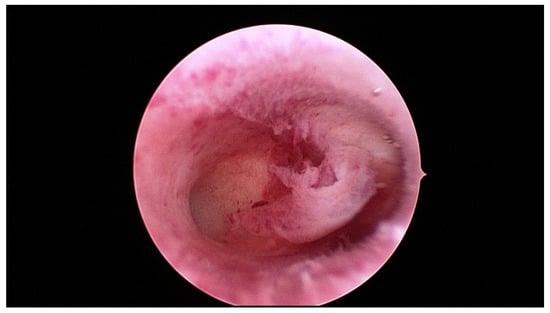

- Pakrashi, T. New hysteroscopic techniques for submucosal uterine fibroids. Curr. Opin. Obstet. Gynecol. 2014, 26, 308–313. [Google Scholar] [CrossRef]

- Casadio, P.; Guasina, F.; Morra, C.; Talamo, M.T.; Leggieri, C.; Frisoni, J.; Seracchioli, R. Hysteroscopic myomectomy: Techniques and preoperative assessment. Minerva. Ginecol. 2016, 68, 154–166. [Google Scholar]

- Tinelli, A.; Favilli, A.; Lasmar, R.B.; Mazzon, I.; Gerli, S.; Xue, X.; Malvasi, A. The importance of pseudocapsule preservation during hysteroscopic myomectomy. Eur. J. Obstet. Gynecol. 2019, 243, 179–184. [Google Scholar] [CrossRef] [PubMed]

- Tinelli, A.; Kosmas, I.; Mynbaev, O.A.; Favilli, A.; Gimbrizis, G.; Sparic, R.; Pellegrino, M.; Malvasi, A. Submucous Fibroids, Fertility, and Possible Correlation to Pseudocapsule Thickness in Reproductive Surgery. Bio. Med. Res. Int. 2018, 2018, 2804830. [Google Scholar] [CrossRef] [Green Version]